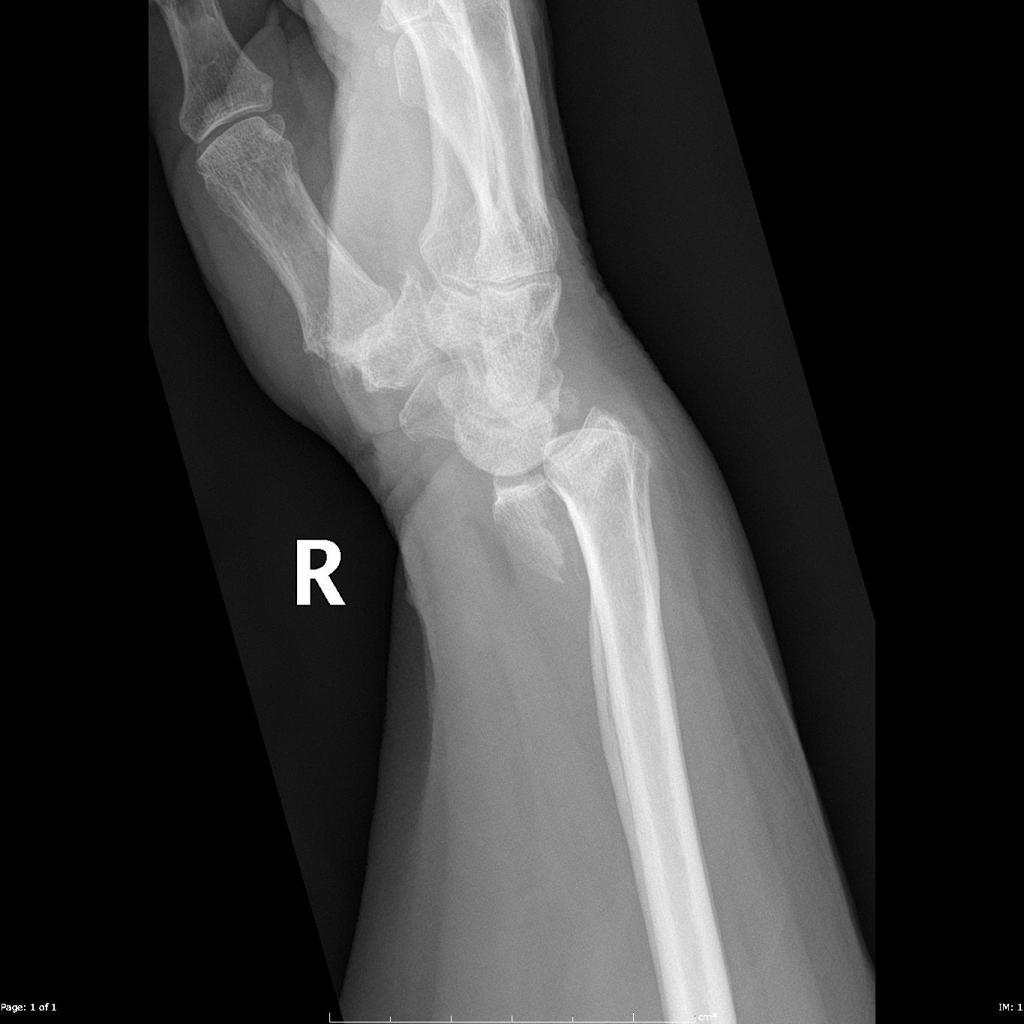

What is a Galeazzi fracture?

Fracture of the radius and dislocation of the ulna at the distal radioulnar joint

Whith any radial shaft fracture, which investigation is mandatory and why?

Lateral X-ray of the wrist

(in case of Galeazzi fracture dislocation)

How are Galeazzi fractures treated?

ORIF

A _________ fracture involves fracture of the ulnar shaft and dislocation of the proximal radial head at the elbow, whilst a __________ fracture involves a fracture of the radial shaft alongside dislocation of the ulna at the distal radio-ulnar joint

A Monteggia fracture involves fracture of the ulnar shaft and dislocation of the proximal radial head at the elbow, whilst a Galeazzi fracture involves a fracture of the radial shaft alongside dislocation of the ulna at the distal radio-ulnar join